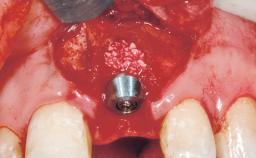

Bone Augmentation Horizontal|Staged

Augmentation Materials Xenogenous|Membrane

Bone Volume Deficient horizontally, requiring prior grafting